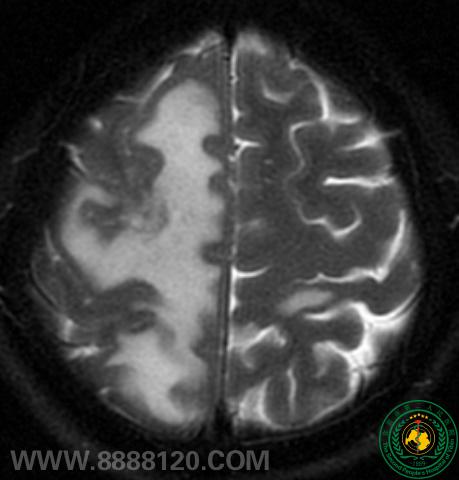

病例2:MRI发现脑转移瘤                       X线胸片右上肺少许炎变                           PET/CT发现右肺门中央型Ca